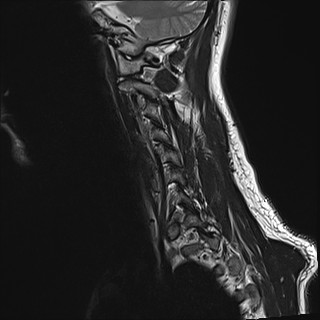

Wirbelsäule HWS

t1_tse_sag